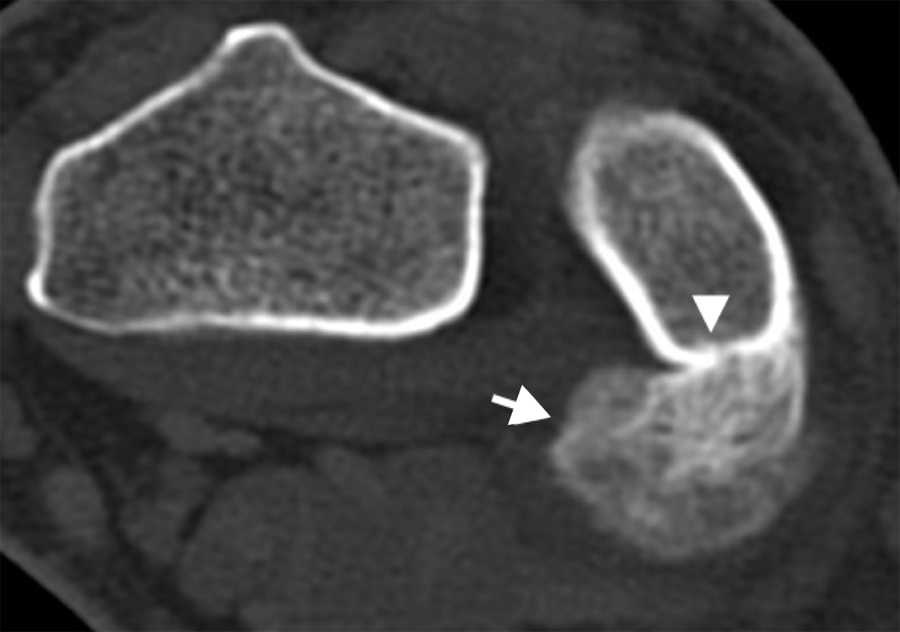

El primer caso se trató de un varón de 35 años con una tumoración en la cara volar de la muñeca derecha, presente desde hacía 2 años, pero que había crecido en los últimos meses. El paciente refería dolor en la muñeca e historia de traumatismo. La radiografía simple mostró una calcificación adyacente al extremo distal del cúbito, sin clara dependencia ósea (no mostrada); mientras que la tomografía computada (TC) corroboró la presencia de una lesión de localización metafisodiafisaria, que evidenciaba continuidad con la cortical ósea cubital posterior, sin afectación medular evidente. La lesión tenía márgenes bien definidos y matriz osteoide (fig. 1). La resonancia magnética (RM) constató la ausencia de afectación de la medular ósea (fig. 2) y el resultado de la biopsia confirmó la POPB.